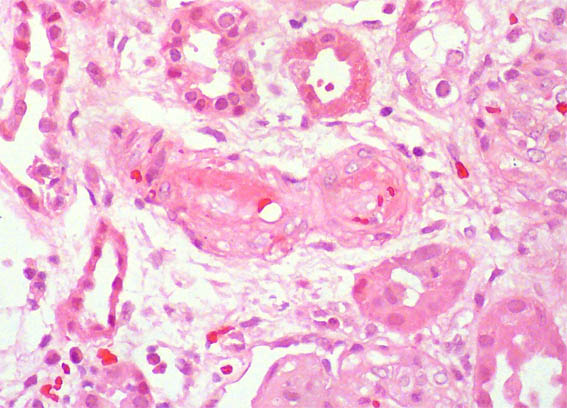

Se hace biopsia renal. Observe las imágenes.

Figura 1. H&E, X100.

Figura 2. H&E, X400.